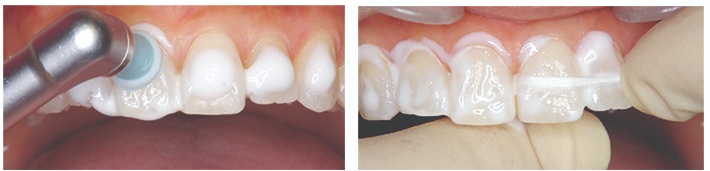

아파프로 케어 과정

🔶치과 프로케어🔶

치면세균막 제거 후 아파프로를

치면에 마사하지 듯 골고루 두포 후

잘 흡수되도록 5~10분간 유지합니다.

🔷가정 자가케어🔷

프로케어 실시 후 일정기간 지속되어야 할 경우

환자분께 아파프로와 개인트레이를 처방드립니다.

약 5분간 치면팩을 진행 후

물로 가볍게 씻어냅니다.

자가사용시 취침전 잇솔질 후 사용을 권장드립니다.